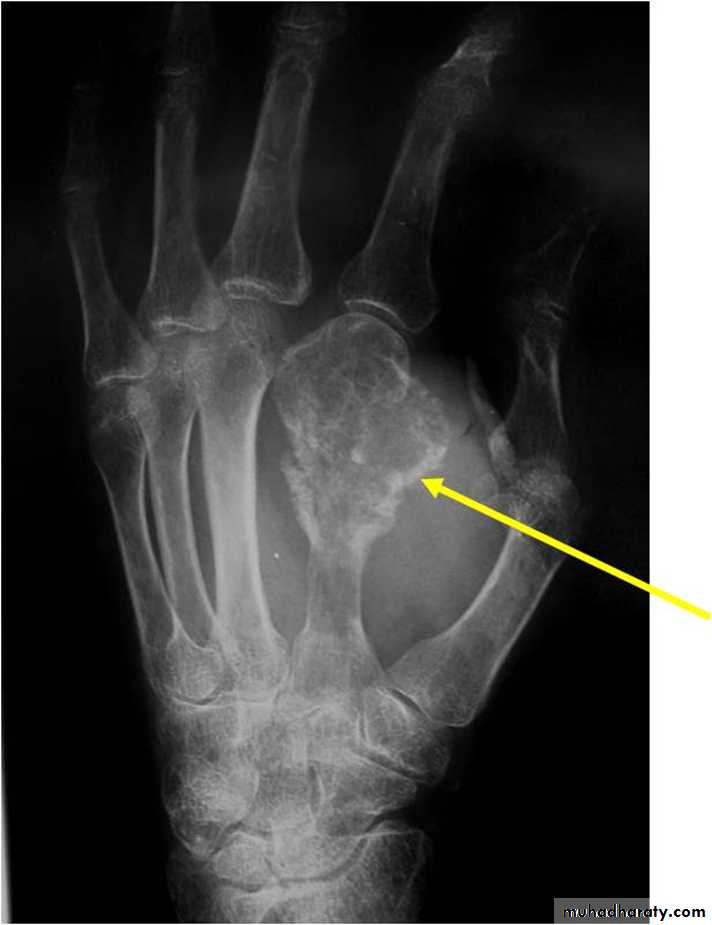

Giant cell tumor:Slowly growing , locally invasive, rarely metastasize.

Age: after closure of epiphysis (20-40 years).

Site: around knee & wrist joints.

Findings:

lytic, expansile lesion,

Sub articular in location,

Not clearly defined margin,

thinning of the cortex (sometimes with destruction of cortex)